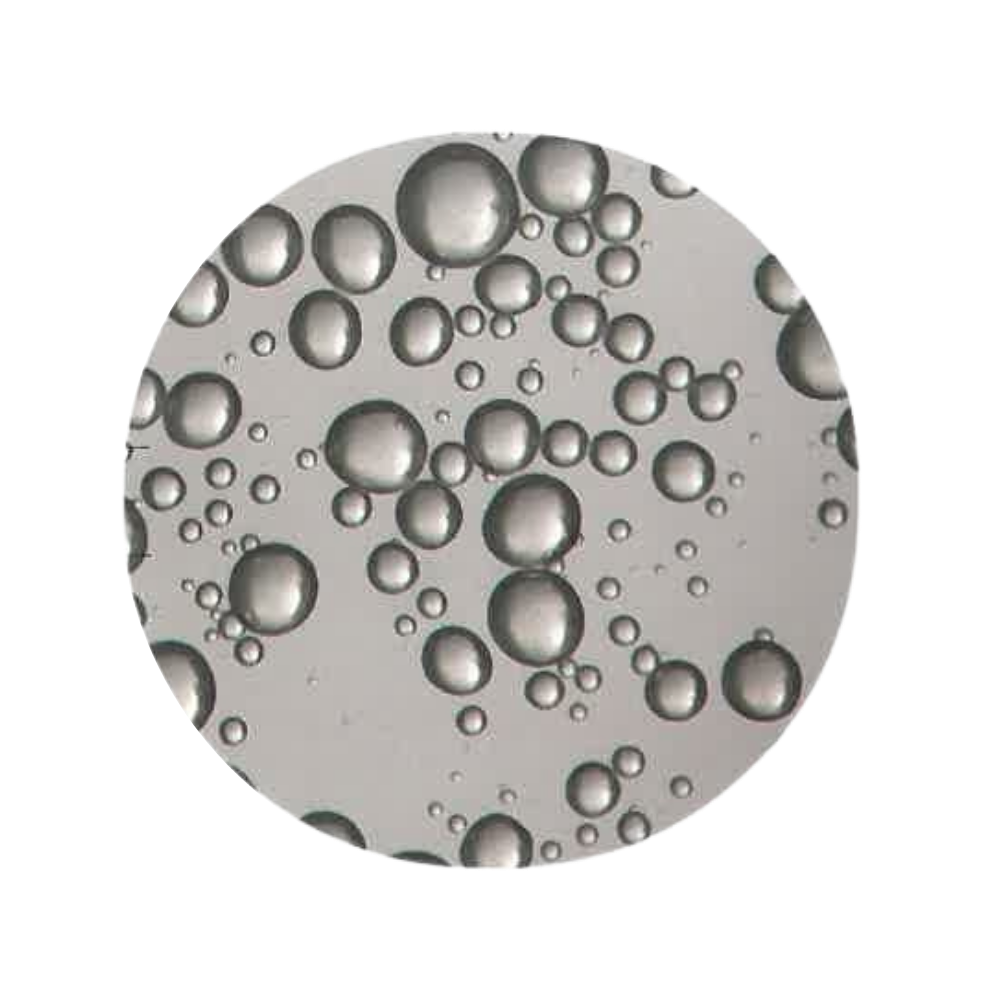

Wet Milling & Spherical Particle Formation

Revanesse® utilises a proprietary wet-milling process, an additional, time-intensive manufacturing step that refines HA into uniform, spherical particles.

Unlike irregular particle structures, spherical HA offers:

- Lower surface area → reduced inflammatory response

- Smoother gel consistency

- Enhanced tissue integration

- Greater predictability during placement

This process is fundamental to achieving subtle, controlled volumisation. The smooth, uniform particles promote better tissue integration and reduce the risk of a foreign-body reaction.